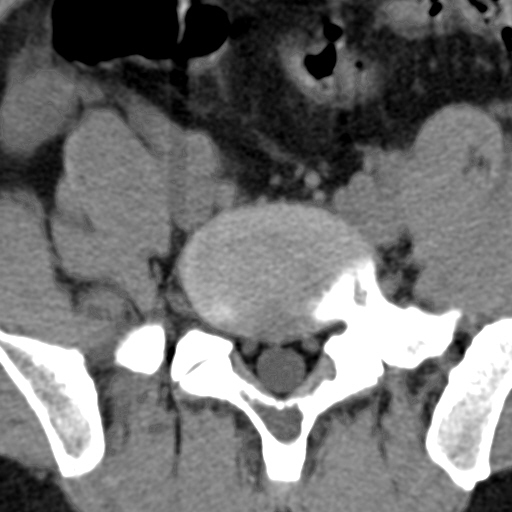

标题: CT4742:椎弓病变,请各位会诊。

男性,37岁,体检发现。

椎弓棘突形态、大小正常,左右椎板及棘突交界区骨质缺损,考虑良性病变(血管瘤可能)。

椎弓棘突形态、大小正常,左右椎板及棘突交界区骨质缺损,边缘清楚,后分见两个小点状高密影,考虑良性病变[血管瘤、成骨细胞瘤,骨纤,骨囊肿]

左右椎板及棘突交界区骨质缺损,周围未见软组织肿块及肿胀,考虑良性病变(血管瘤可能)。

破坏区呈彭胀性 切有硬化缘 考虑良性占位  囊肿可能性大